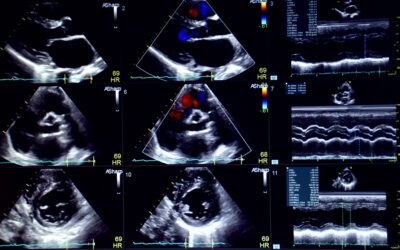

What Are the Differences Between EKGs & Echocardiograms

If you have been issued an echocardiogram or EKG that you will get at Hollywood Diagnosticss Center in South Florida, it's important to have a basic...

Does Medicare Pay for My Echocardiogram

An echocardiogram, or echo, is a test that uses sound waves to create a picture of the heart while in motion. The results show the shape and size of...